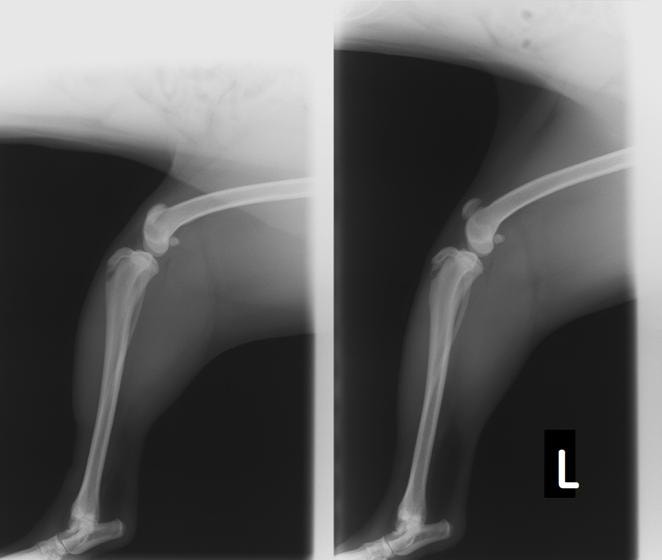

■ 症例24 キャバリア 7か月

左右膝蓋骨内方脱臼(左:グレードⅣ 右:グレードⅢ)

以前から左右後肢の跛行が認められ、整形外科学的検査・レントゲン検査により左右の膝蓋骨脱臼が認められた。症状が重度である左膝の膝蓋骨脱臼整復術を行った。外科手技は縫工筋及び内側広筋の解放、脛骨粗面の外側転位、滑車ブロック形造溝術、内外側関節方の縫縮を実施した。術後一か月時点で、左の膝蓋骨は安定しており経過は良好である。

本症例は成長期における重度の膝蓋骨脱臼であり、術後の再発の可能性もあるため、経過をしっかりと観察していく必要がある。また、今回手術を実施していない右膝に関しても経過を観察し、手術を検討していくこととする。